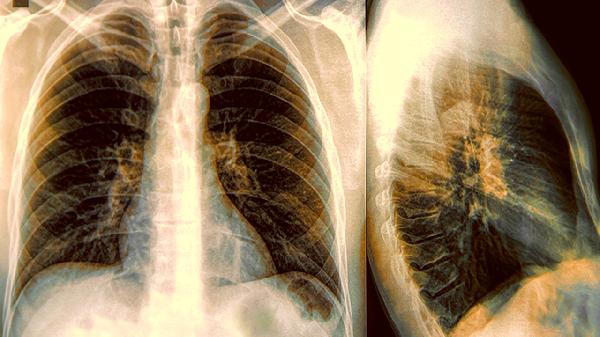

2、肿瘤分期:早期肺癌Ⅰ期、Ⅱ期通过手术切除和辅助治疗,5年生存率可达60%以上。中期肺癌Ⅲ期5年生存率约为30%至40%。晚期肺癌Ⅳ期已发生转移,5年生存率不足10%。

3、治疗方式:

手术治疗:适用于早期患者,包括肺叶切除术、全肺切除术和楔形切除术。

放射治疗:用于无法手术的患者或术后辅助治疗,包括外照射治疗和立体定向放射治疗。

化学治疗:用于中晚期患者,常用药物有顺铂、卡铂和紫杉醇。